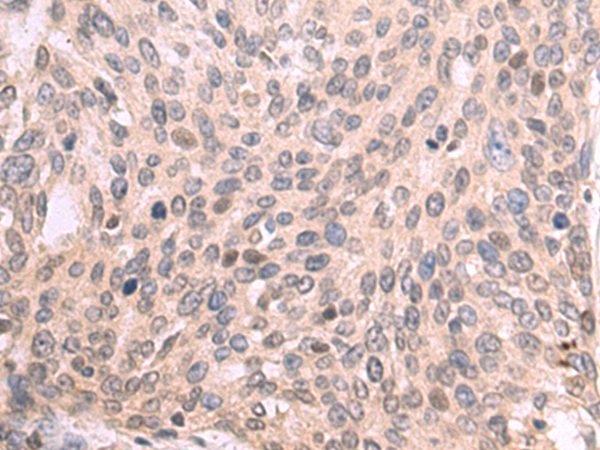

分类: 科研抗体货号: P07521别名: PAK5应用: IHC反应种属: Human, Mouse